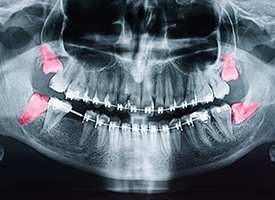

Most people are born with four wisdom teeth, one for each quadrant of the mouth. However, it’s possible only to have one, two, or three, and some lucky individuals are born with none!